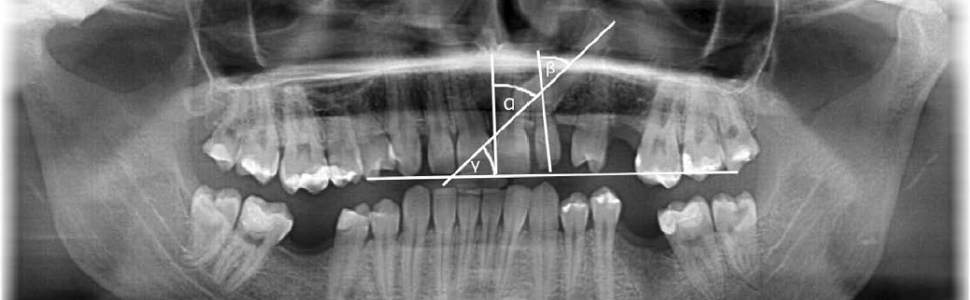

Wstęp. Kły szczęki stanowią drugie pod względem częstości zatrzymania zęby (1-3% populacji), zaraz po zębach trzonowych trzecich. Podczas ektopowego wyrzynania się kłów szczęki może dojść do resorpcji korzeni zębów sąsiednich, ankylozy kła i formowania się torbieli. Wykrywalność resorpcji zębów sąsiadujących z ektopowo wyrzynającym się kłem wzrastała na przestrzeni ostatnich lat z powodu częstszego wykorzystywania badania CBCT w diagnostyce radiologicznej. Resorpcja korzeni zębów sąsiadujących z wyrzynającym się ektopowo kłem szczęki dotyczy najczęściej zębów siecznych bocznych, osiągając różne wartości: od 7,7% do 66,7%.

Introduction. Maxillary canines are the second most frequently impacted teeth (the prevalence ranges from 1 to 3% of the population), just after the third molars. Ectopic eruption of maxillary canines can cause different complications, such as: root resorption of adjacent teeth, ankylosis of the canine and formation of a cyst. Detection capability of root resorption of adjacent teeth during ectopic eruption of maxillary canines has been increasing over recent years because of more frequent use of CBCT for radiological diagnosis. Root resorption is the most common in lateral maxillary incisors, it reaches different values from 7.7% to 66.7%.